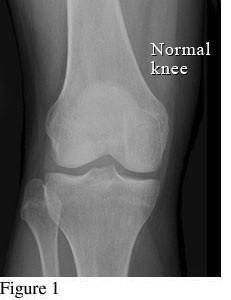

Hình ảnh so sánh giữa khớp bình thường và khớp bị thoái hóa khớp gối

Để phân biệt các giai đoạn của bệnh thoái hóa khớp gối, cần dựa vào phim X- quang theo tiêu chuẩn chẩn đoán thoái hoá khớp của Kellgren và Lawrence như sau:

1. Giai đoạn 1: Thoái hóa khớp gối độ 1

Hình ảnh khớp gối trên phim X-quang: Khe khớp gần như bình thường, có thể có gai xương nhỏ.

Ở giai đoạn đầu tiên, khớp gối chưa có dấu hiệu bất thường cho thấy bị thoái hóa khớp gối. Bệnh nhân đi lại bình thường, chưa xuất hiện cơn đau khớp hoặc có thể chỉ đau khớp gối khi đứng lên ngồi xuống, ngồi xổm, lên xuống cầu thang. Khớp gối cũng chưa bị sưng và không biến dạng. Nếu chụp thêm MRI có thể thấy khớp gối gần như bình thường.